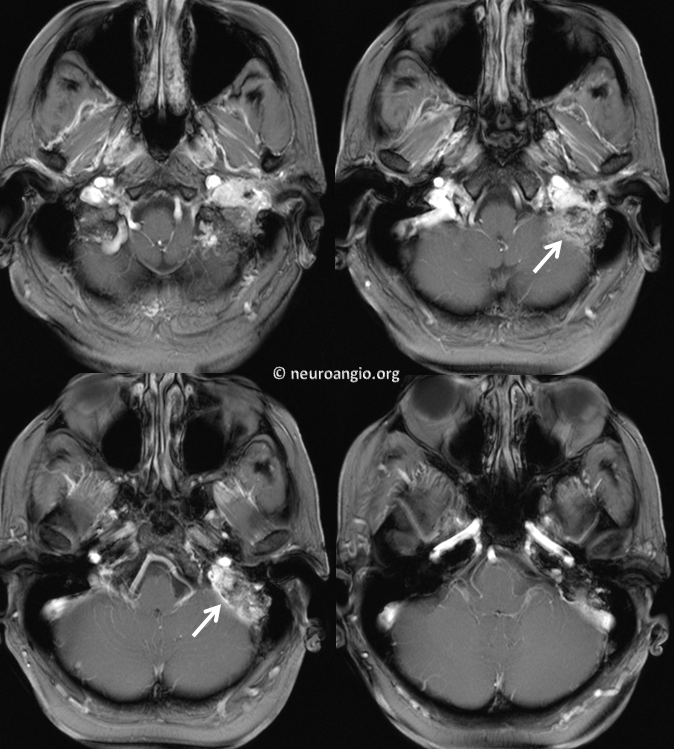

From neuroangio.org

Pulsatile Tinnitus Glomus Jugulare Tinnitus Brain Tumor Tinnitus is a very common symptom of acoustic neuromas and many other inner ear conditions. In other cases, the tinnitus can sound like hissing, buzzing or roaring — like when putting a seashell to the ear. It is described as a benign tumour because it cannot spread into the brain. Tinnitus — or ringing in the ears — and dizziness. Tinnitus Brain Tumor.